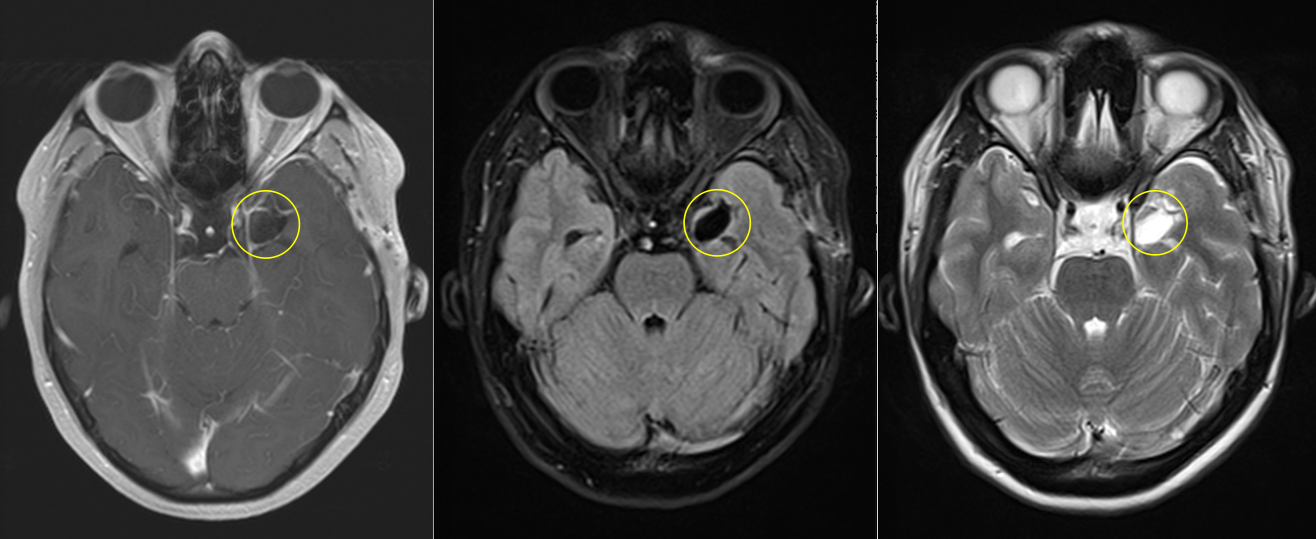

Pentru pacienți, aceste episoade sunt adesea greu de înțeles și pot fi însoțite de teamă și incertitudine. Investigațiile imagistice au adus însă explicația: RMN-ul cerebral a evidențiat o mică tumoră profundă, situată pe fața internă a lobului temporal stâng, la nivelul hipocampului și al nucleului amigdalian.

Deși tumora era relativ mică – aproximativ doi centimetri – localizarea ei era extrem de delicată. Hipocampul este una dintre structurile centrale ale creierului, implicată în memorie și procesarea emoțiilor, iar lobul temporal stâng joacă un rol important în limbaj.